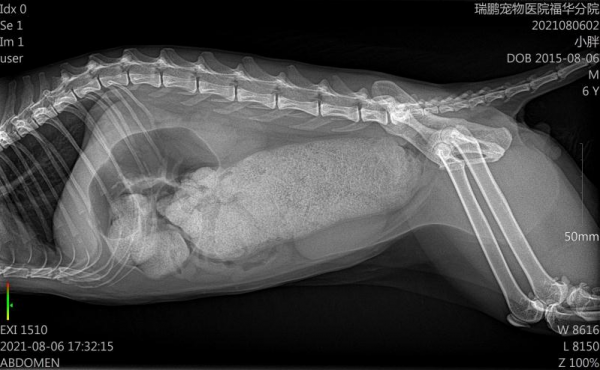

吳醫生也安排喵喵進行了DR影像檢查,透過結果可以看到,喵喵結腸段堆積了好多便便,已經影響到了升結腸、橫結腸、降結腸。

綜合所有檢查結果,吳醫生斷定,橘喵是患上了特發性巨結腸。